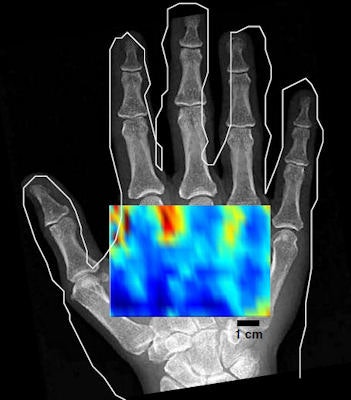

After beam characterization and transmission measurements, images of a phantom and a hand were acquired in vivo using the transducer and a broadband microphone receiver. An image of three 3-mm wooden rods in a water phantom, scanned axially, demonstrated the tomographic reconstruction approach, albeit with some image distortion and artifacts. In vivo noncontact imaging of a hand was demonstrated with a conventional C-mode approach that produces images for a fixed depth below the skin. The low-resolution scan shows varying contrast between the anatomy containing mainly bone and that containing only soft tissue.